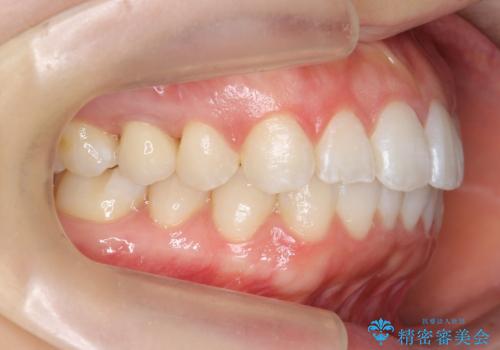

前歯のがたつき インビザラインで

治療症例の内容

- 前歯のがたつきを治したいとのことでした。歯を抜かずにできる範囲で引っ込めたいとのことでした。

歯列の側方拡大(横に広げる)と、エナメル質の削合で並べました。

歯を抜いているわけではないので、口元はそこまで変化はありませんが、前に出すことなくデコボコは取れたと思います。